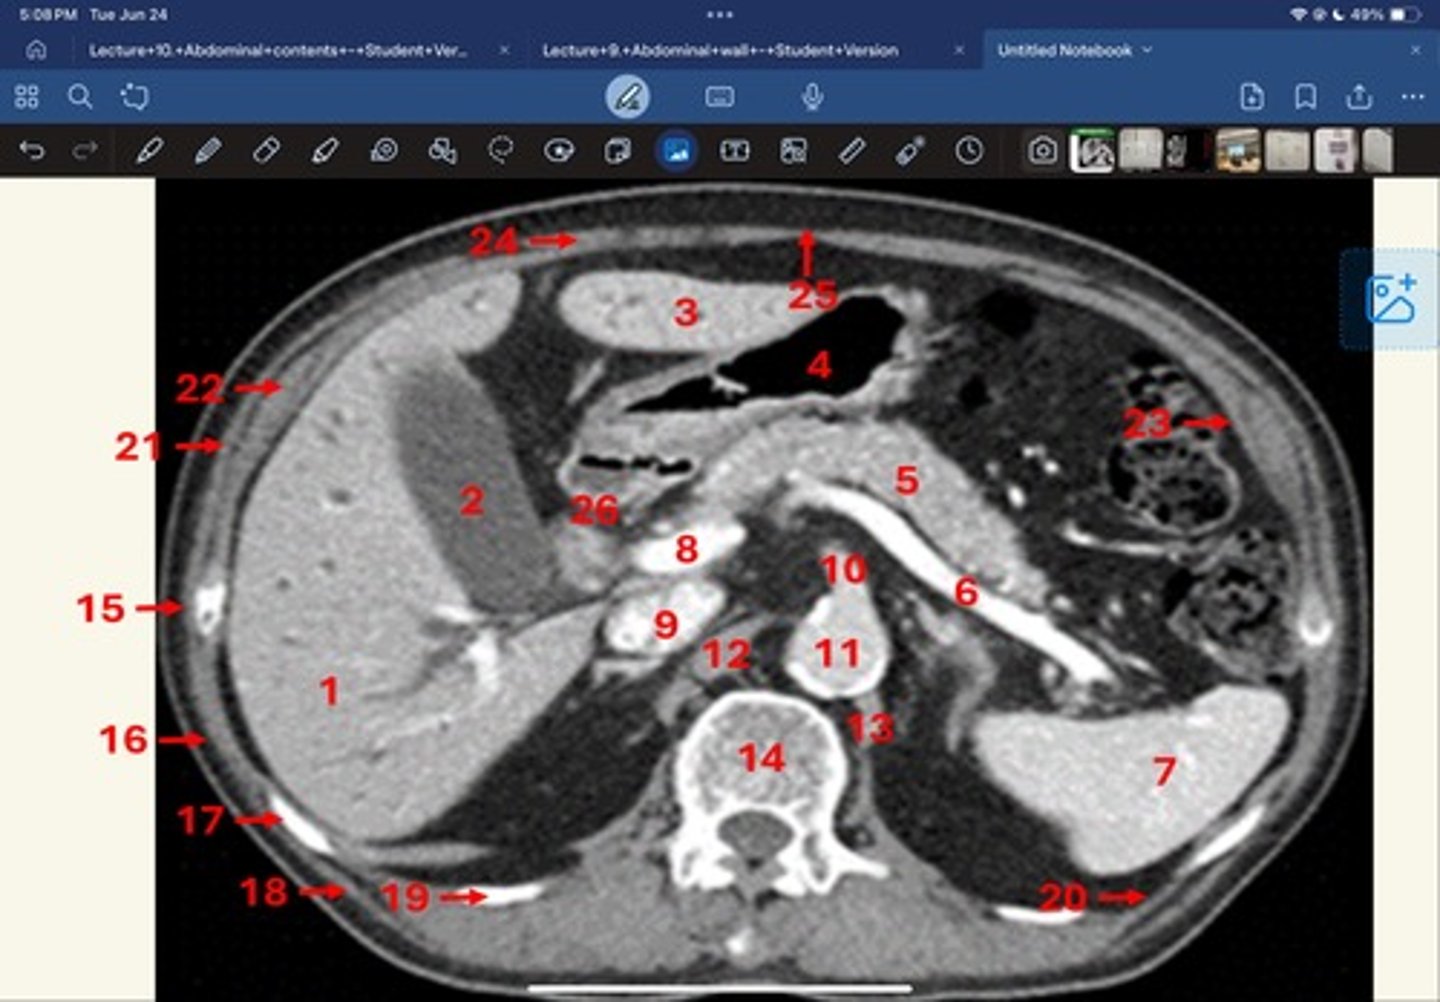

Right lobe of liver

What is 1

Gallbladder

What is 2

Left lobe of liver

What is 3

Stomach, pylorus

What is 4

Pancreas

What's 5

Splenic vein

What's 6

Spleen

What's 7

superior mesenteric vein

What's 8

Inferior vena cava

What's 9